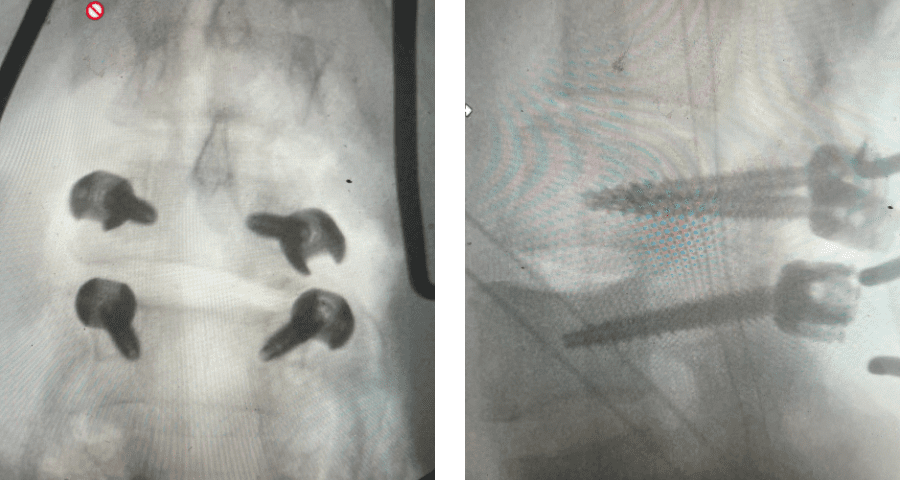

Here is a dramatic example of a patient who had prior laminectomy and fusion surgery four years earlier, and now presents with low back pain with severe burning pain in her right lower extremity pain. She did not respond to epidural steroids. She had a prior L3-S1 laminectomy, and an L3-5 instrumented fusion. A current MRI (Fig 4) demonstrated severe L2-3 next segment stenosis due the development of massively hypertrophied or enlarged L2-3 joint complexes. There was also a grade 1 retrolisthesis of L2 on L3 with a large anterior disc osteophyte complex. The configuration of the stenosis was worse in the right lateral recess secondary to the anterior osteophyte and more right-sided facet compression of the thecal sac, correlating with the patient’s right-sided symptoms. When the anatomy correlates with the patient’s symptoms that is the best set up for success. It was decided to offer a revision surgery to the patient, who agreed.

Fig 4: Sagittal and axial T2-weighted lumbar MRI images demonstrating severe next segment degeneration and stenosis at L2-3 above prior L3-5 fusion. Note retrolisthesis and significant facet arthropathy at L2-3 (red arrow).

Revision surgery is more involved than primary surgery. In order to start decompressing this large complex, you must develop a plane; you have to find the edge of sometimes a remnant of a lamina or the lamina that can be buried in scar. You must carefully dissect the edge with a sharp upbiting curette and then either using a sharp Leksell to start removing this lamina or use a fine Kerrison to widen the plane and exposure and begin to expose the normal ligamentum above. In this case it was critical to expose and decompress the L3 nerve roots bilaterally. What is quite helpful is finding the inferior edge of the L2 facets. Then one must lift up the inferior L2 process up with a curette and simultaneously insert a Kerrison into joint space and remove the whole facet process. This is a great move because it allows access to the plane between the superior facet and the descending nerve root and a starting point to fully decompress the nerve root. Because of scarring there often is not a clear plane in order to accomplish the decompression. Care is taken to make sure there is a clear separation between edge of bone and dura during the process of inserting a Kerrison edge. The important part of this is feeling your opening and actually using your Kerrison as a dissecting tool once an edge has been established to perform a foraminotomy. We were able to remove the inferior L2 facet process with impunity as we knew we were performing an instrumented fusion to L2. The patient’s had a prior L3-5 instrumented fusion which upon exploration was solidly fused. It was decided to remove her prior hardware as it served its purpose and add a short segment from L2-3 (Fig 5). Patient did well after her surgery with relief of her right leg pain.

Fig 5: intraoperative fluoroscopic images demonstrating L2-3 screw placement.